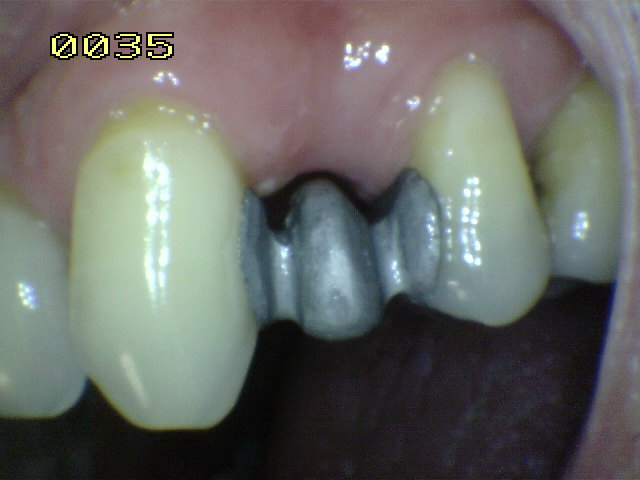

El material oscuro es una

amalgama cubierta por el diseño del puuente; observe los restos

de cemento adherido al esmalte dental.

Caries de esmalte y dentina

en el otro pilar (flechas rojas)